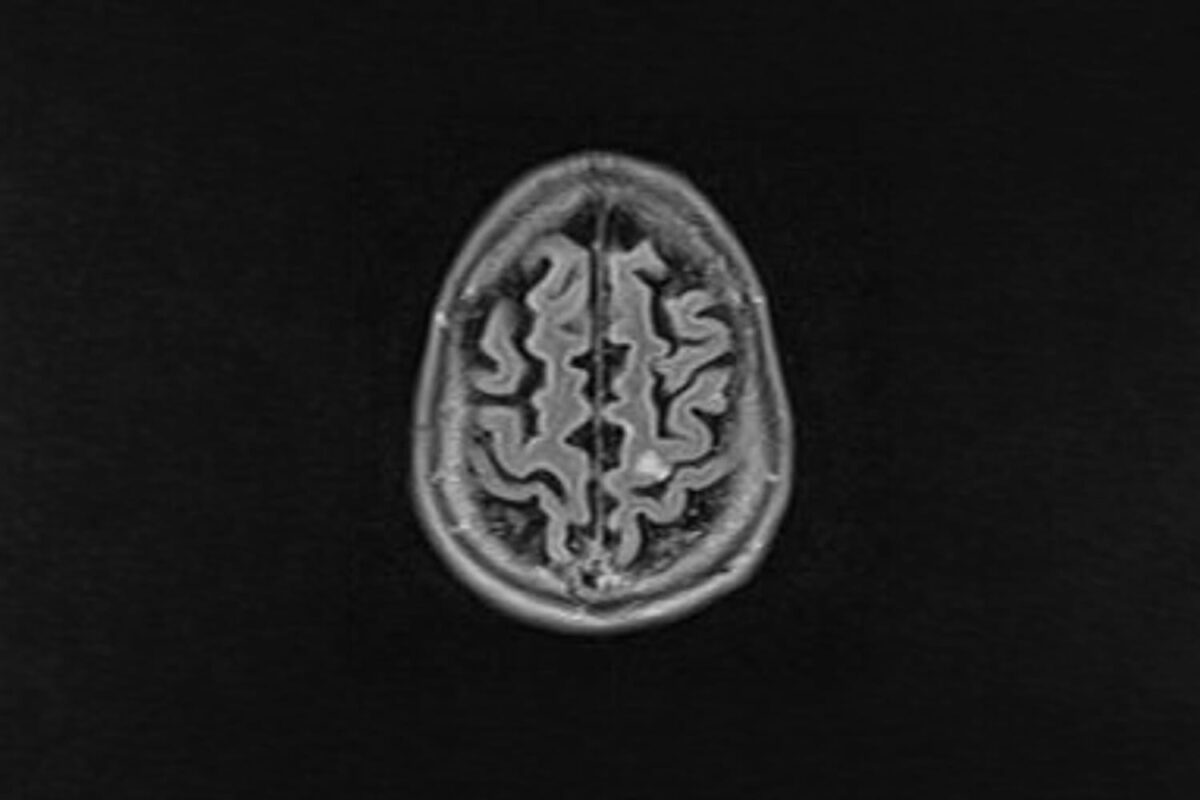

A ressonância magnética feita 24 horas após a internação mostrou a área afetada no lado esquerdo do cérebro, o que explica os sintomas no lado direito do corpo. Uma área pequena, graças à rapidez do atendimento.